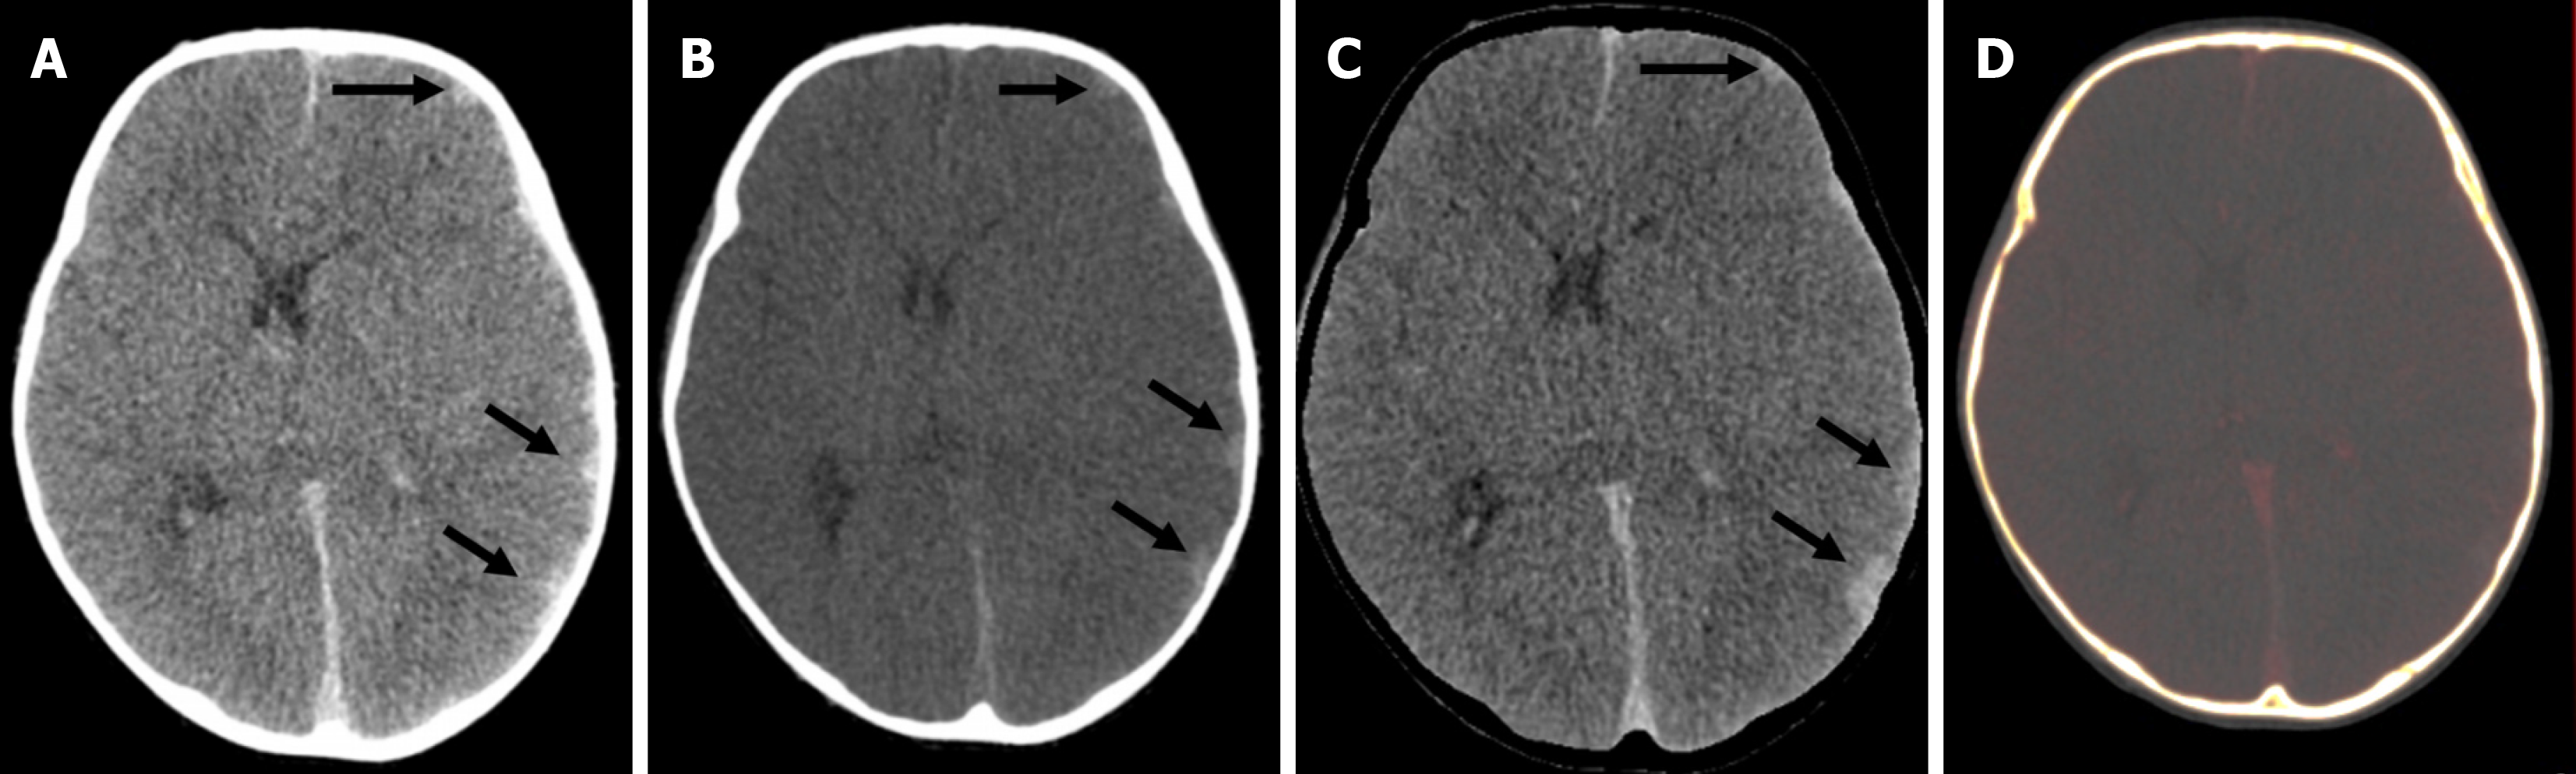

Figure 7 A 4-year-old male with hemophilia A who presented with acute headache and neck rigidity.

A: Axial mixed-enhanced CT head images showed subtle extra-axial high-density lesions (indicated by arrows) in the left frontal and parietal lobes, resulting in a slight midline shift to the opposite side; B: The virtual non-contrast image confirmed that the hyperdensity (arrows) represented an acute bleed and not abnormal enhancement; C: Bone removal tool of dual energy demonstrated the bleed more clearly (arrows); D: Iodine overlay image did not show any iodine uptake in the region of the bleed.